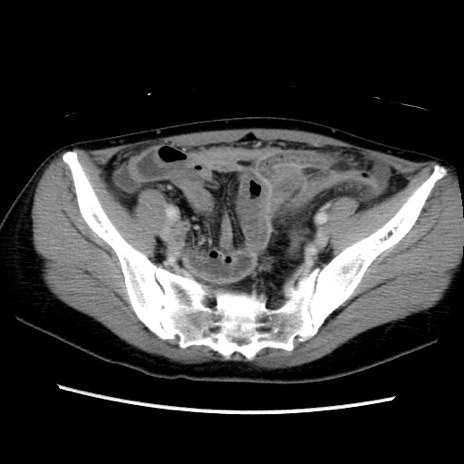

症例39(横断像)

【症例】40歳代女性

【主訴】上下腹部痛

【現病歴】2日目から下腹部痛あり。夜間は痛みで眠れなかった。昨日より上腹部痛と下痢が出現。臥位で痛みは軽快したため、休んでいた。本日になって臥位でも立位でも痛みが強くなってきたため救急要請。

【既往歴】子宮内膜症

【身体所見】部:平坦・軟、左上下腹部に圧痛あり、反跳痛あり。

【データ】WBC 21800、CRP 26.78